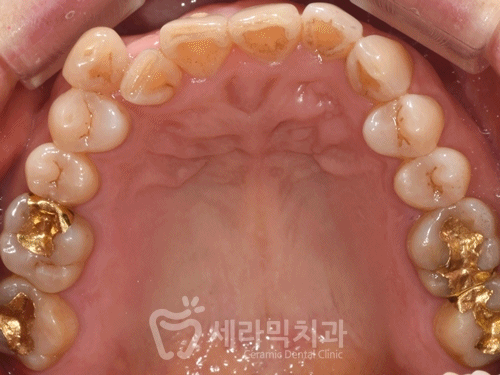

(4) 50대 치아교정 치료 결과

(실제 교정치료 기간 : 16개월)

① 치열불규칙 개선

삐뚤빼뚤하던 치열이 가지런하게 개선되었습니다.

② 앞니 반대교합 개선

아래 앞니가 위 앞니를 덮고 있던 반대교합이

정상교합으로 개선되었습니다.